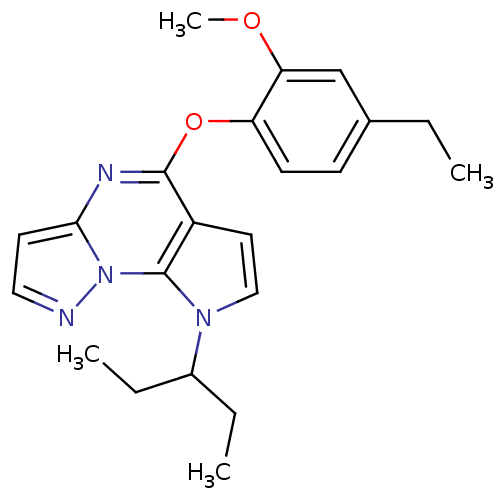

TargetCorticotropin-releasing factor receptor 1(Rattus norvegicus (rat))

Minase Research Institute

Curated by ChEMBL

Minase Research Institute

Curated by ChEMBL

Affinity DataEC50: 2.60nMAssay Description:Antagonist activity at rat CRF1 receptor expressed in CHO-K1 cells assessed as CRF-stimulated cAMP accumulation by enzyme immunoassayMore data for this Ligand-Target Pair